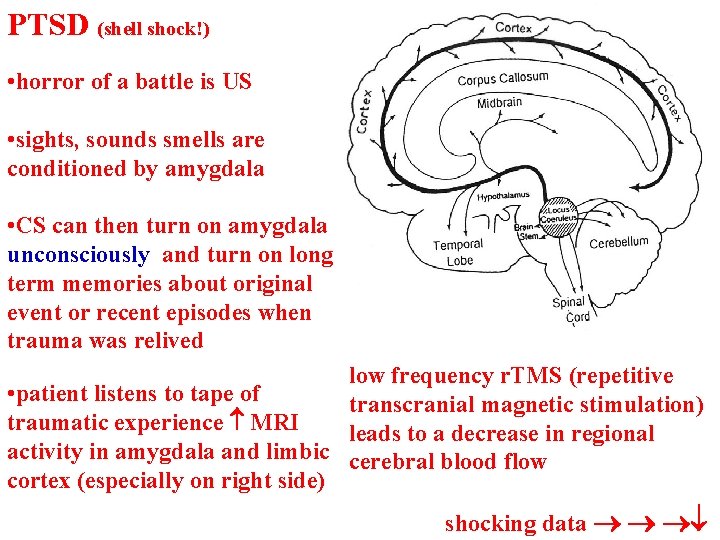

PTSD (shell shock!) • horror of a battle is US • sights, sounds smells are conditioned by amygdala • CS can then turn on amygdala unconsciously and turn on long term memories about original event or recent episodes when trauma was relived low frequency r. TMS (repetitive • patient listens to tape of transcranial magnetic stimulation) traumatic experience MRI leads to a decrease in regional activity in amygdala and limbic cerebral blood flow cortex (especially on right side) shocking data